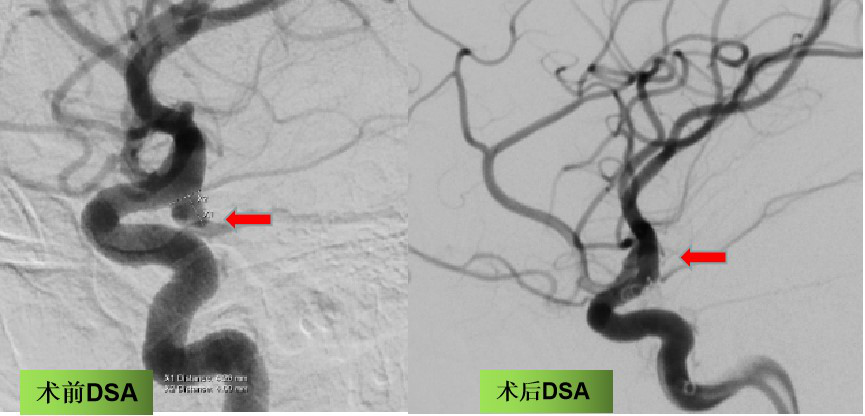

4名患者中,最年轻的一位年仅36岁。突发的头痛、头晕,持续有10余小时症状不缓解后到北京清华长庚医院急诊就诊。经脑部CT成像,可疑右侧后交通动脉动脉瘤,紧急行全脑血管造影,术中确认为后交通动脉起始段动脉瘤,开颅手术夹闭风险较高,经与家属沟通后行支架辅助弹簧圈动脉瘤栓塞术,手术过程顺利,患者术后1天恢复良好,无明显神经功能障碍,生活基本自理。

手术前后脑血管造影,提示动脉瘤栓塞满意